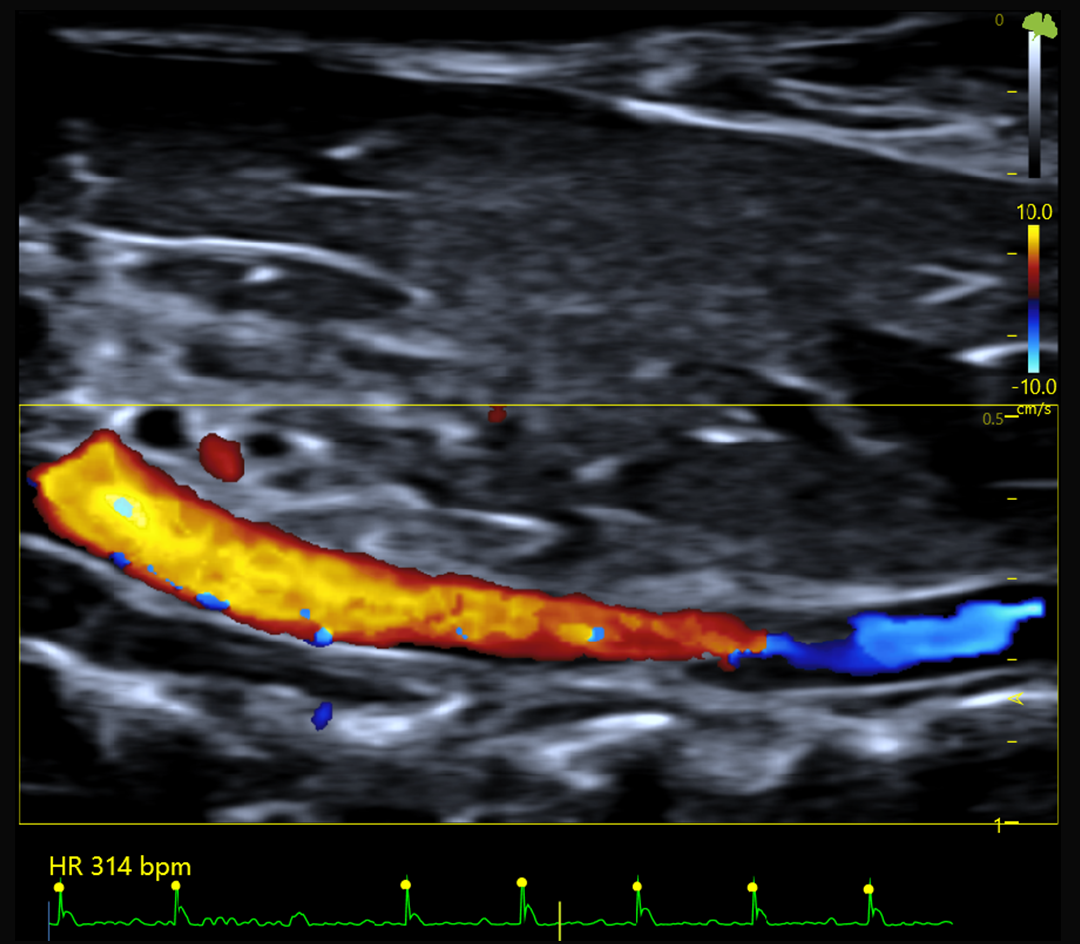

Hémodynamique et flux sanguins

Doppler couleur, pulsé et puissance

Doppler couleur, Doppler pulsé et Doppler puissance